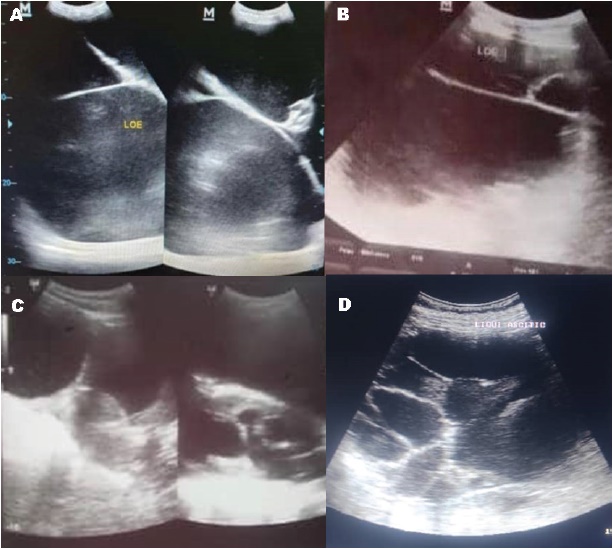

MM, 57 years, consulted the Autonomous Service University Hospital of Maracaibo (OGS-ASUHM) or Maternity Dr. Armando Castillo Plaza, Venezuela, on October 29-20, due to dyspnea at medium exertion and increased volume in the abdomen, from eight months before. Genital bleeding of the meno-metrorrhagia type of moderate quantity, bright red, without clots, not fetid. Abdomen: AC: 125 cm, palpable tumor of approximately 90 x 80 cm, non-mobile, non-painful, ascites is evident; preoperative laboratory tests: normal. Abdominal-pelvic US: evidenced from the xiphoid region to the hypogastrium, a large lesion occupying liquid content, multi-located with echoes of medium echogenicity, rounded, poorly defined irregular contours, without vascularization, measurement by quadrants with an approximate diameter of 41.7 x 35.0 x 35.7 mm (Fig. 2A). Conclusion: Injury occupying the abdominal-pelvic space. Admission diagnoses (October 29-20): Giant tumor of the left ovary. 2. Chronic arterial hypertension. On November, 13-20 an exploratory laparotomy was performed with the following operative findings: 1. Giant tumor of the left ovary with cystic content, approximately 100 x 100 cm, with an estimated weight of approximately 15 kg. upon inspection. 2. Left oophorectomy was performed, and the frozen biopsy reported papillary mucinous cystadenoma, which was negative for malignancy. 3. Right ovary without alterations. 4. Abdominal cavity lavage was performed. 5. The abdominal cavity was closed. Postoperative evolution was expected, and was discharged on the 13th postoperative day (November, 26-20). The anatomopathological study (December, 04-20) reported a left ovarian tumor that measured 30 x 25 cm, and weighed 46.738 lb (21.200 kg), with a diagnosis of mucinous cystadenoma of the left ovary (Fig.1A). The immediate, mediate, and late (June 2021 and November 2022) postoperative controls were normal.

SMPP, 43 years old, was admitted to OGS-ASUHM on April 08-22 for presenting dyspnea at medium exertion and increased volume in the abdomen 3 years earlier. The abdomen was globular, distended, and had an ascites wave. Abdominal-pelvic US (11, 29-19): large lesion occupying abdominal-pelvic space, of probable ovarian etiology (Fig. 2B), simple cyst of the left ovary, uterine fibroids. MRI (February, 04-20): Abdominal-pelvic space occupation lesion. Giant ovarian cyst. Tumor markers (January 24-20): β-chorionic gonadotropin, alpha-fetoprotein and CA-125 normal. Admission diagnoses (April 08-20): Giant ovarian tumor. Plan: 1. Laboratory tests 2. Admission for surgery. On April, 18-22 an exploratory laparotomy was performed with operative findings: 1. Giant right ovary tumor, with a cystic appearance, estimated weight of approximately 30 kg. 2. Endometrial polyp of 2 x 1 cm., without macroscopic evidence of malignancy. A right oophorectomy was performed, and the frozen biopsy reported serous cystadenoma, negative for malignancy. Total abdominal hysterectomy, left oophorectomy, and appendectomy were performed. Abdominal cavity lavage was performed. Normal postoperative evolution. Discharged on the 18th postoperative day (May 06-22). Weight at discharge: 95.019 lb. Anatomopathological report (May, 20-22): tumor that measured 30 x 25 cm, weighed 65.256 lb. (29.600 kg), right ovary serous cystadenoma (Fig. 1B). Immediate and mediate postoperative medical controls were normal.

BBIG, a 16-year-old adolescent, was admitted to OGS-ASUHM on 04, 20-22 due to increased abdominal volume. Abdomen, palpable supra-umbilical mobile tumor, not painful. β-HCG: 4.33 U/ml, CA-125: 48.70 U/ml, CA-19.99: 6.85U/ml., Alpha-fetoprotein: 4.16 ng/ml, CEA: 1ng/mL. Abdominal-pelvic US: space-occupying lesion of probable ovarian nature, rule out the retroperitoneal origin, correlate with abdominopelvic CT (Figure 2C). Abdominal-pelvic computed tomography: image of probable ovarian nature, hypodense, with regular contours, density similar to liquids, thin walls, measuring approximately 36.2 x 25 x 16.2 cm. and covering the entire abdominal and pelvic region. On 04, 21-22 an exploratory laparotomy was performed, showing a giant cystic tumor of the right ovary, which measured approximately 40 x 50 cm. and weighed 26.675 lb. (12.100 kg) (Fig. 1C). The transoperative frozen biopsy reported papillary serous cystadenoma, without evidence of malignancy. Postoperative evolution was satisfactory, and she was discharged in good general condition on 04 25, 2022, 5th postoperative day.

L.O.A., 64 years old, consulted on March 2023 for an increased volume in the left abdominal iliac fossa region of progressive growth 6 months ago, without extenuating circumstances. Concomitantly refers to pain in that area. She was evaluated, and an abdominal-pelvic tomography imaging study was indicated, which reported a cystic tumor in the pelvic cavity. Elective surgery was planned. Ca 19-19: 15 (0-47), CA-125:

41 (0-35), verified value. Abdominal-pelvic computed tomography (CT): (March 03-23): tumor of cystic appearance, large size, occupying the pelvic cavity extending to the upper abdomen of 27x 20cm., in diameter with a displacement of neighbouring structures and highly suggestive of ovarian tumor. Liquid collection, incipient ascites at the level of the pelvic cavity. Abdominal US (march 14-23): suggestive signs of giant mucinous type cystic tumor. Minimal ascites (Figure 2D). Chest X-ray PA (July,14-23): Slight elevation of left hemidiaphragm. Cytology and ascitic fluid cell block (March, 13-23): chronic inflammatory smear with reactive mesothelial changes. Evaluation by oncologic surgery (March, 22-23): GOT, scant ascites. Dx Admission: GOT. Surgical intervention (August, 05-23): exploratory laparotomy: ovarian protocol. Findings: 50 mL inflammatory fluid, tumor of left ovary, 70 x 50 cm, firmly adherent to the left uterine horn, cystic, of mixed consistency. Uterus, right ovary, right uterine tube: normal. Procedure: Peritoneal fluid sampling, tumor exteriorization, total abdominal hysterectomy with tumor inclusion, right salpingo-oophorectomy, vaginal vault closure, right and left parietocolic slide, right and left diaphragm and prevesical fascia and Douglas pouch sampling, omentectomy, appendectomy, plane synthesis, placement of drains in subcutaneous cellular tissue, asepsis and final cure. Tumor histological type (biopsy): serous cystadenoma, benign, weight: 27.116 lb (12.300 kg) (Fig. 1D). Hospitalization for 48 hours with satisfactory clinical evolution.